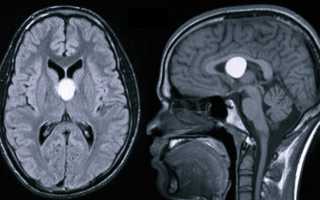

- Пинеальная киста – шишковидное тело, которое может иметь разные размеры. Ее диагностируют примерно у 1-4% пациентов. Характерным симптомом заболевания является возникновение достаточно сильной головной боли в случае поднятия глаз кверху, но у большинства людей киста не вызывает дискомфорта.

- пинеальная. Развивается в эпифизе, диагностируется достаточно редко, но может нарушить обмен веществ, негативно влияет на зрение и координацию. Ее развитие провоцирует эхинококкоз либо закупоривание выводящих путей, из-за чего нарушается отток гормонов эпифиза. Она вызывает водянку мозга и его воспаление. При наличии этого образования человек ощущает боли в голове, неспособность ориентироваться на местности, постоянное желание спать, раздвоение изображения перед глазами и проблемы с ходьбой. Если такая симптоматика не наблюдается, есть вероятность, что киста не будет увеличиваться. Этот тип кистовидного образования находят в 4% случаев во время томографического исследования по совсем другим поводам. На начальных этапах пинеальную кисту лечат медикаментами, в запущенном состоянии – хирургическим методом. Осложнением может стать мозговая водянка;

На сегодняшний день основными методами диагностики и последующего прогноза данной болезни являются МРТ (магнитно-резонансная томография) и КТ. Полученная томограмма показывает состояние всех составляющих мозга (эпифиза, мозжечка, гипофиза, нервных ганглий и других частей). С ее помощью можно увидеть место расположения перивентрикулярного глиозного очага и атрофических рубцовых следов внутри головного мозга без вскрытия черепной коробки, оценить их форму, размеры и интраселлярный рост.

Кроме того, данные способы обследования позволяют сделать дифференциальную диагностику промежуточного состояния между доброкачественной кистой и злокачественной опухолью. После внутривенного введения специального контрастного вещества его продукт накапливается в опухолевых тканях, а киста при этом не становится контрастной.